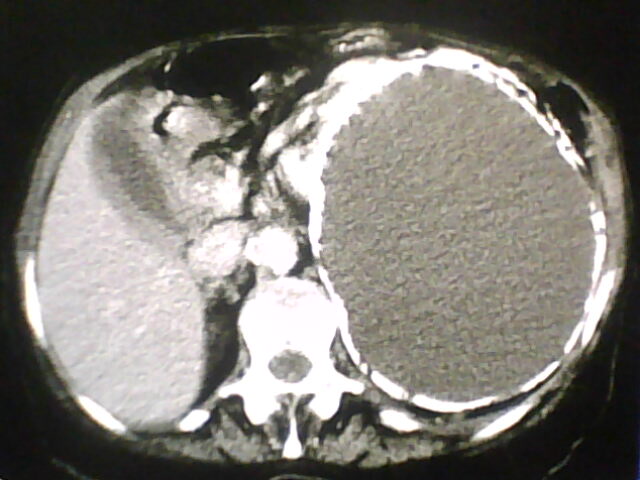

Paciente 77 anos com quadro de dor abdominal e vômitos a três dias.

Nos cortes axias grande massa de densidade de líquido, ocupando a metade esquerda do abdome e deslocando as alças intestinais para baixo e para direita. Apresenta contornos de paredes calcificadas em íntimo contato com o parênquima renal esquerdo.

Reconstrução coronal e sagital mostra o tamanho da lesão de conteúdo cístico e nível aéreo, justificando assim desconforto sentido pela paciente.